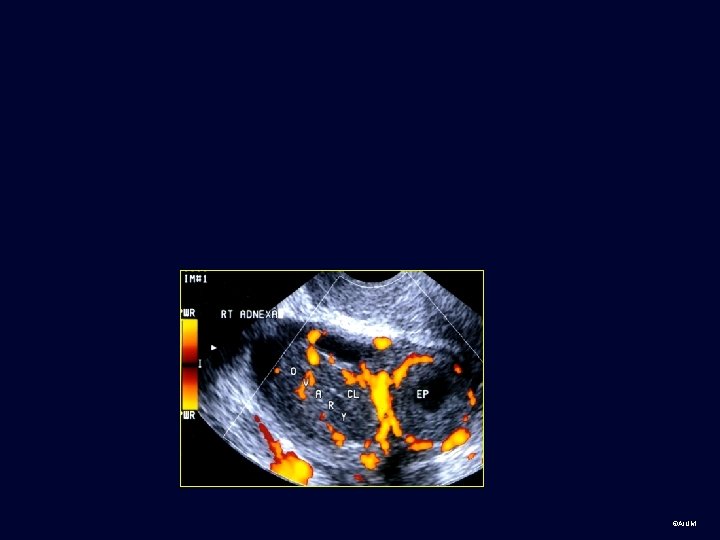

Technique • The standard pelvic examination • Composed of the traditional transabdominal approach (TAS) • Combined with transvaginal sonography (TVS) • Frequently using Doppler sonography ©AIUM

Example of Color and Spectral Doppler Ultrasound § Flow to the transducer is shown in red and away in blue. Cursor Line § The Doppler sample volume (oblique arrow) shows the sampling site for pulsed Doppler interrogation. § The right panel shows spectral Doppler of umbilical artery flow. As the flow is toward the transducer, it is depicted as positive or upward deflections. Umbilical artery Doppler waves ©AIUM

Practice cases for students: Normal and abnormal • Transabdominal, transvaginal or can’t tell? • Body part? • Normal or abnormal (provide diagnosis or Ddx if possible) ©AIUM